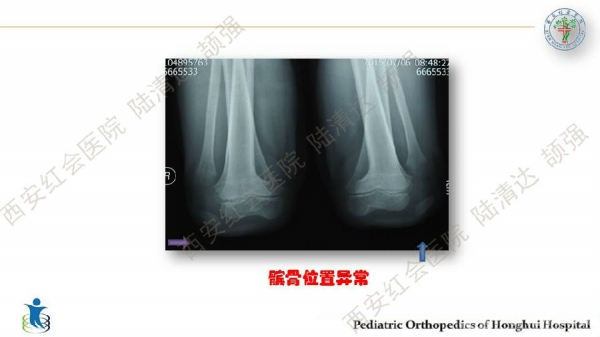

习惯性髌骨脱位,多见于儿童,女性多于男性。临床表现主要为行走步态难看、下肢无力、易摔跤等,而反复摔跤的病史常是患者就诊的主诉。其病理特点主要膝关节内外侧伸肌肌群不平衡及局部结构发育异常,表现为:股外侧肌及膝外侧软组织挛缩,髌韧带附着点偏外,股内侧肌群萎缩无力及MPFL发育不良,髌股关节滑车发育不良及膝外翻畸形等。习惯性髌骨脱位的治疗,建议早发现早治疗。不仅能有效解决脱位问题,还可避免继发畸形。如治疗延误,可出现髋、膝关节继发屈曲、腰前凸加大等畸形。甚至膝关节骨性关节炎,影响工作与生活。